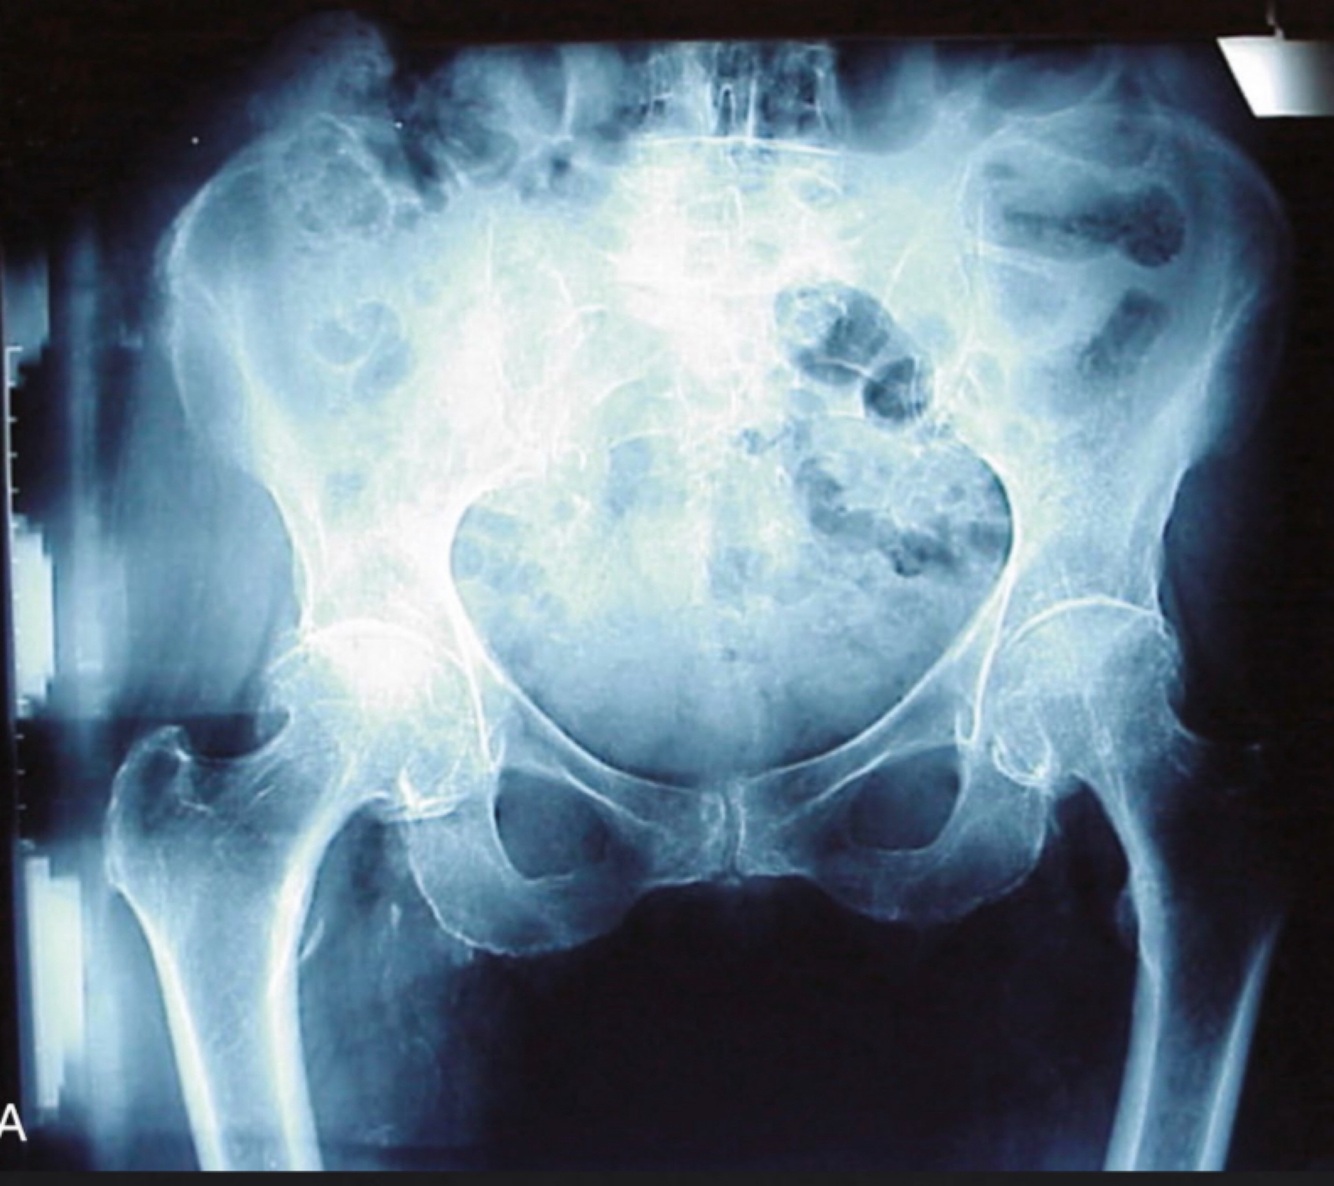

Example 2: On a Agfa system an exposure of 85 kVp at 40mAs of a CTL hip resulted in a lgM of 2.0. What change in mAs is needed to bring the lgM to the median of 2.6?

Double the mAs TWICE (40x2= 80, 80x2= 160) to get the exposure indicator (IgM) to. 2.6 -Explanation: The lgM is the logarithm of the median exposure. The median exposure for this system is 2.6. The exposure indicator is directly related, therefore a lgM of 2.0 is underexposed. For each doubling of the mAs a 0.3 increase of the lgM would result. If the radiographer increase the mAs 4X to 160 mAs, this change would increase the lgM by 0.6 and bring it to about 2.6, which is the median suggested by the manufacturer.